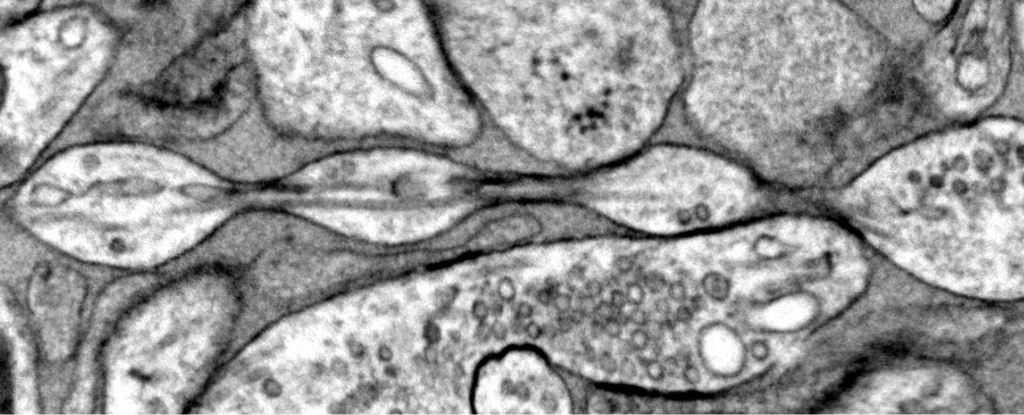

Zdroj Foto: Quan Gan/Mitsuo Suga/Shigeki Watanabe

Predchádzajúce štúdie zistili, že keď sú mozgové bunky poškodené alebo odumierajú, axóny môžu začať „bublinkovať“ a vytvárať vzor podobný perlám. „Axonálne perličky“ sa vyskytujú najmä v mozgu ľudí s Alzheimerovou alebo Parkinsonovou chorobou. Tím z Univerzity Johnsa Hopkinsa však tvrdí, že perly, ktoré našli v mozgoch myší, sú v nanorozmeroch, nie v mikrorozmeroch ako v predchádzajúcich prípadoch axónových perličiek.

Analýzou rezov mozgu myší v rôznom veku výskumníci priblížili jednotlivé axóny bez ochranného obalu. Bez ohľadu na to, ako boli plátky mozgového tkaniva kultivované, axóny nevyzerali hladko, ale boli posiate „nanoperlami“ rôznych veľkostí. Navyše bolo možné manipulovať s veľkosťou týchto perál a predpovedať výsledky.

Odstránenie cholesterolu z axónu napríklad viedlo k menšiemu množstvu perál a zníženej schopnosti posielať elektrické signály. Niektorí kritici si však myslia, že nanoperly pozorované v myších neurónoch sú reakciou na stres spôsobený kultiváciou tkaniva.

Vedúca autorka Jacqueline Griswoldová povedala, že jej tím preto zobrazil aj živé bunky, ktoré neboli zmrazené alebo chemicky pripevnené. Tie takisto ukázali nanoperlový vzor. Pri experimentoch Griswoldovej chemikália, ktorá sa zvyčajne používa na zobrazovanie neurónov, spôsobila, že nanopearly zmizli, čo možno vysvetľuje, prečo neboli predtým pozorované. Štúdia bola publikovaná v časopise Nature Neuroscience.